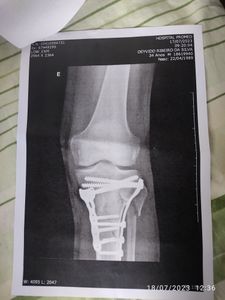

Olá, sofri um acidente e quebrei a perna esquerda, fiz cirurgia e estou com 2 platinas, como sou autônomo estou sem trabalhar e sem dinheiro para custear o tratamento, aluguel da muleta, fisioterapia e dentre outros!

Preciso ficar 120 dias de recuperação, quem puder ajudar, fico agradecido e que Deus abençoe grandemente sua vida 🙏🏾